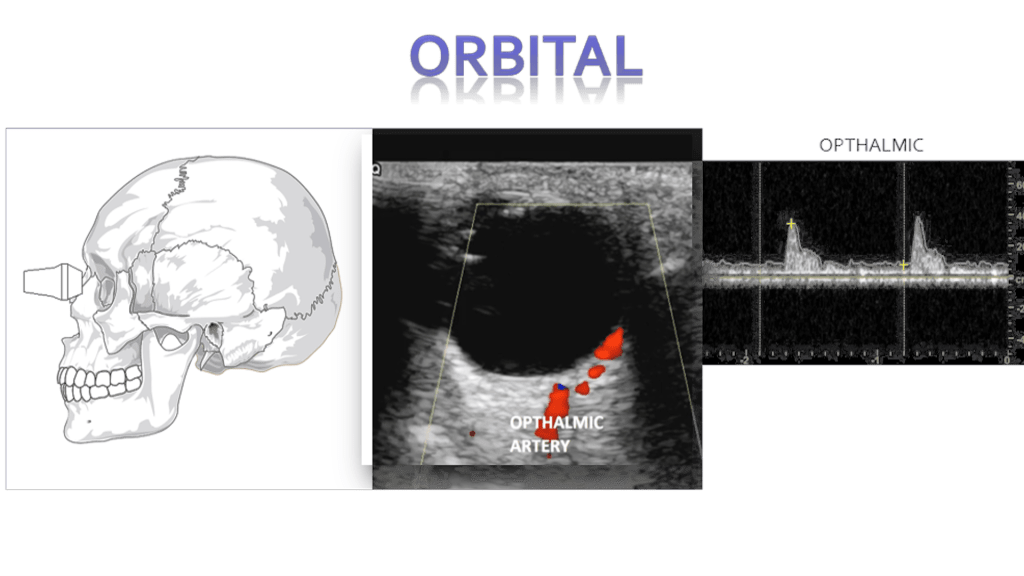

Central Retinal Artery Occlusion

Blockage of the central retinal artery usually due to an atherosclerotic thrombus (typically from an internal carotid artery plaque). Presents with sudden, painless, partial or complete monocular loss of vision. Also associated with giant cell arteritis. Patient describes “shade” or “curtain” coming down over entire visual field in the affected eye. Bilateral presentation is rare.

Sonographically you’ll encounter an echogenic foci posterior to the optic disc “bright dot sign” with lack of color or spectral flow distal to the thrombus